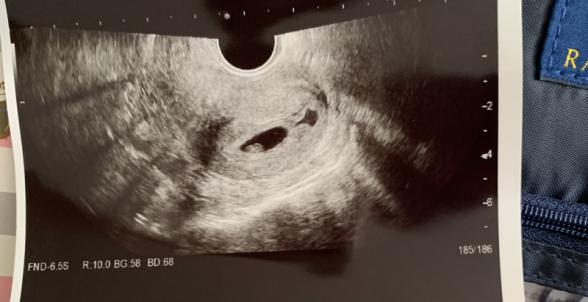

本日のエコー写真添付しておきます。

胎嚢の右側にある黒い影が出血と言われました。